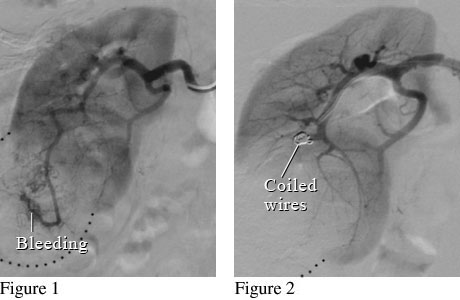

Angiogram image of a renal mass

Figure 1 shows a kidney with a large mass that is bleeding. Figure 2 shows small coiled wires that have been placed in the artery to block the bleeding.